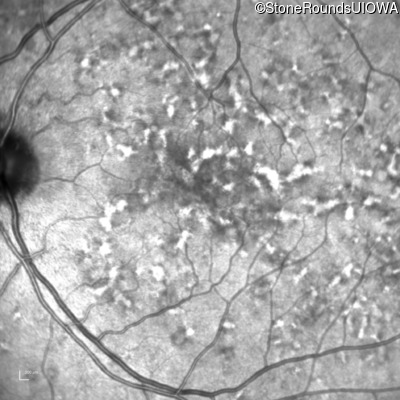

Age at visit: 49 years

This 49 year old man was first told he had a fundus abnormality on a routine eye exam at age 34. Ten years later he noticed some distortion just superior to fixation.

Pattern Dystrophy PRPH2 Gln239Stop CAG>TAG   AD